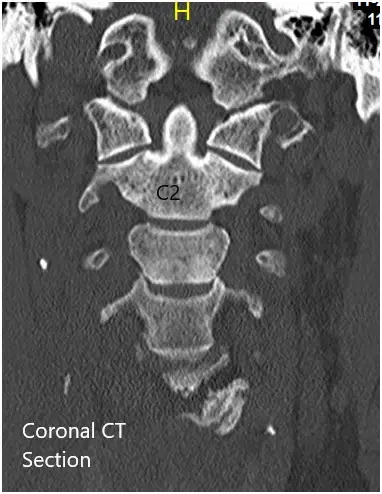

CT of the cervical spine demonstrated multilevel posterior disc bulges with bilateral neural foraminal stenosis of the mid to lower cervical spine. Sclerotic hypertrophic degenerative changes were associated with the mid to lower cervical facets.

Preoperative Coronal and Axial CT sections.